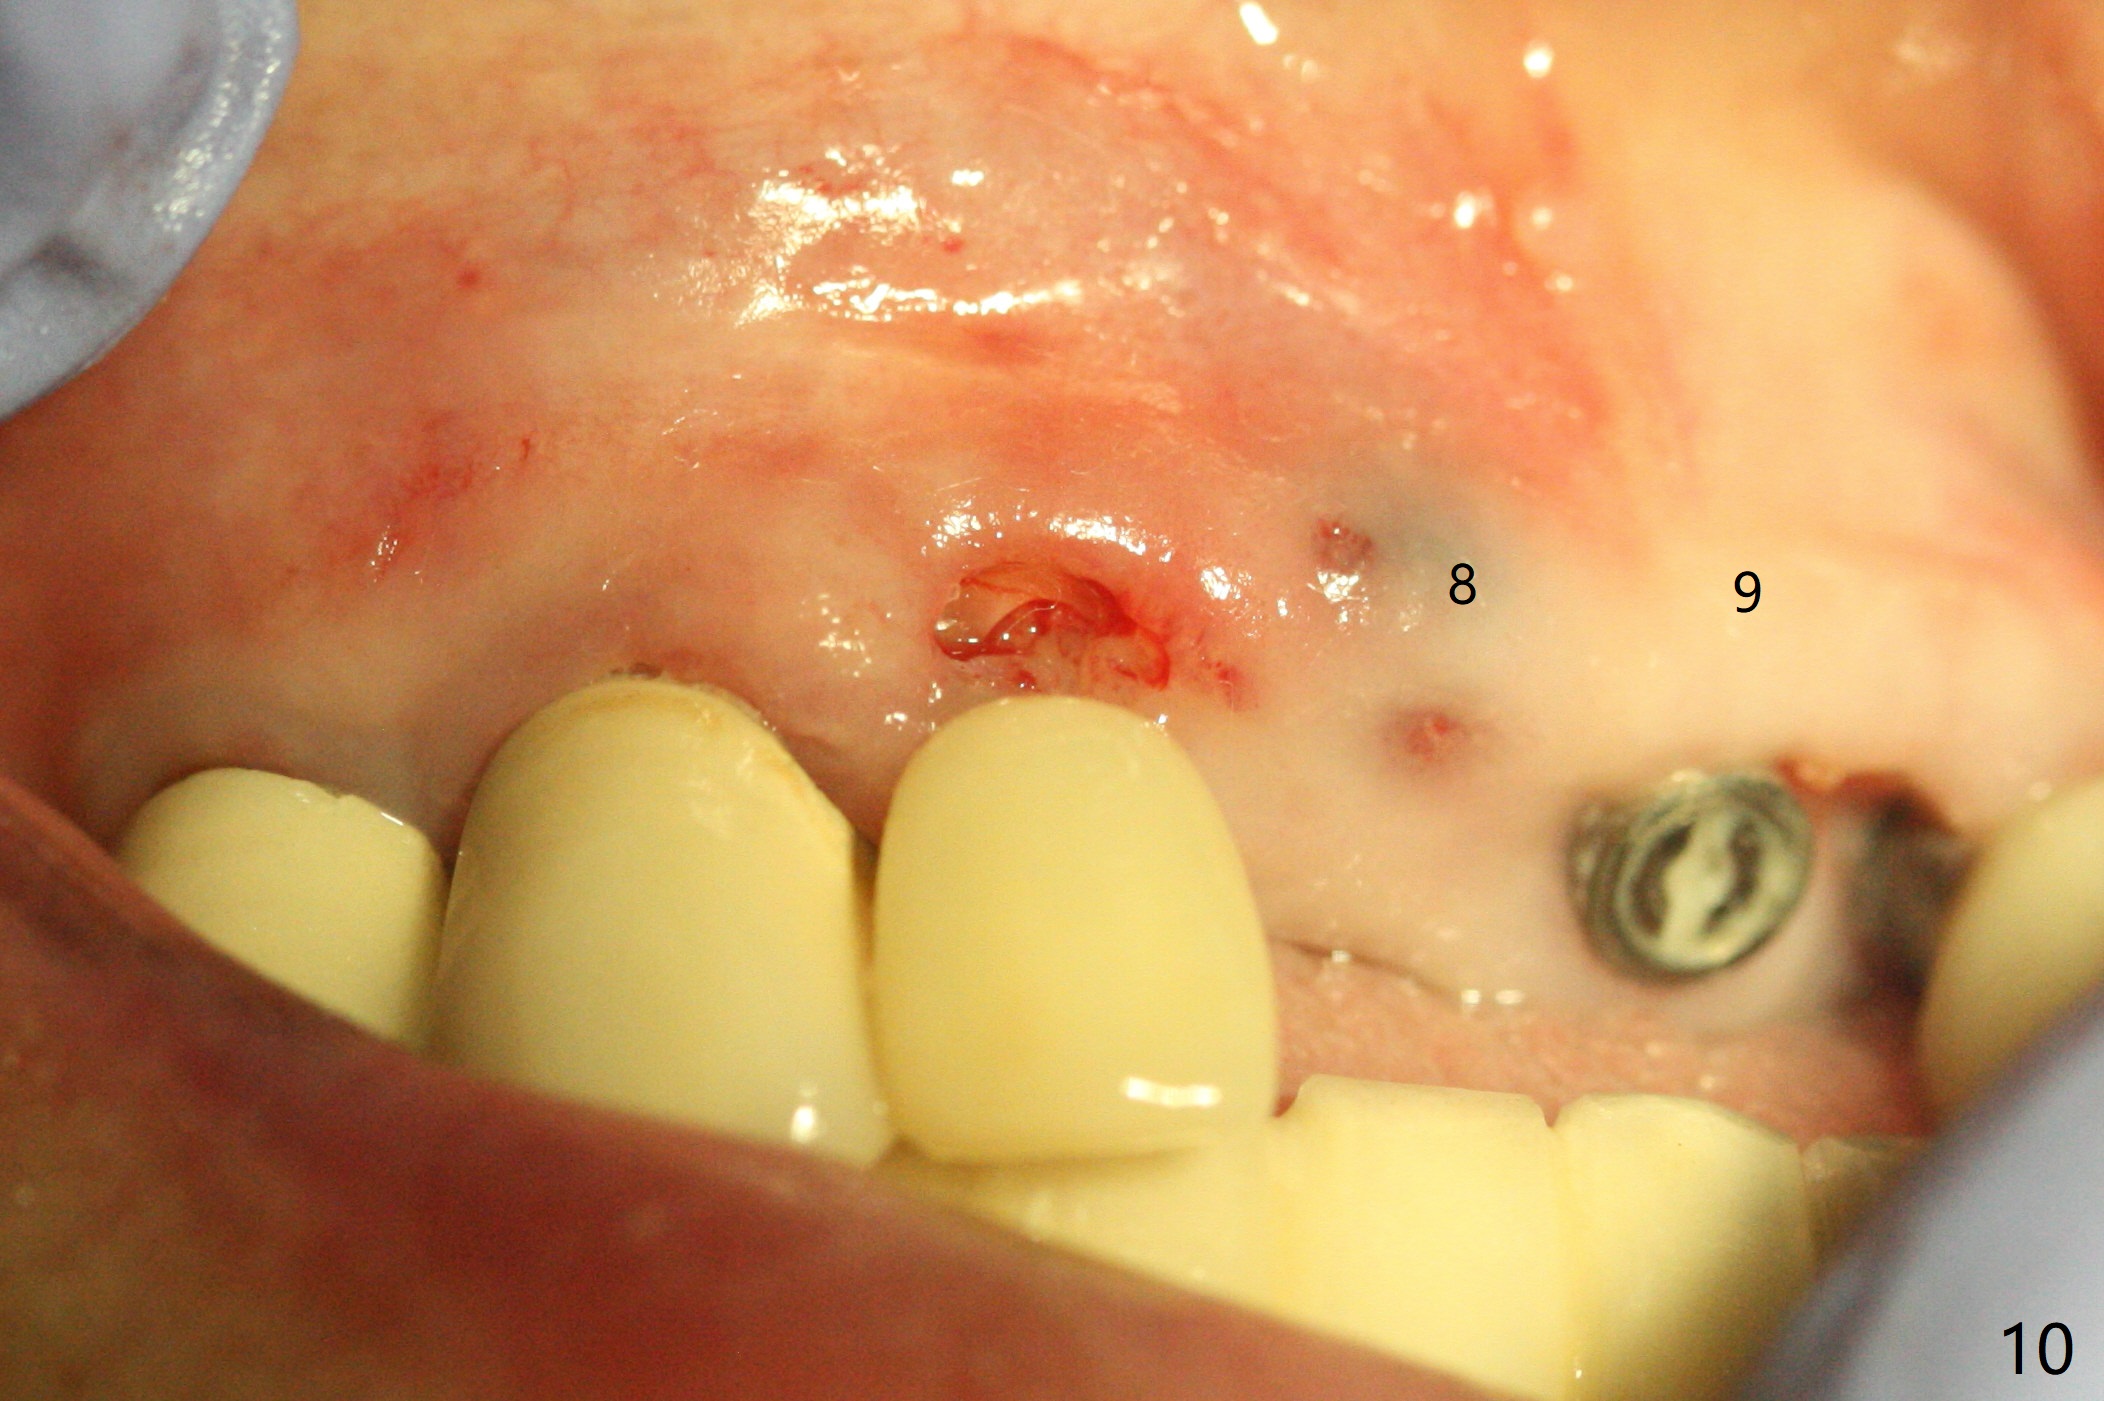

The edentulous area at #7 is narrow both buccopalatally and mesiodistally, whereas the crowns of the neighboring teeth are long (Fig.1,2). For the latter reason, it is difficult to remove the apical portion of the root, including gutta percha with surgical handpiece (Fig.3 *) for socket shield (Fig.2 *). To avoid the perspective implant touching socket shield, initial osteotomy is palatal. When a 2 mm drill is being used, the coronal end of the palatal plate starts to perforate. A 2.5x14 mm 1-piece implant is placed with 30 Ncm (Fig.4). The palatal plate is thin (Fig.5). Preop CT will help determine the position of initial osteotomy. The buccal gingiva seems to have been re-attached to the underlying alveolus and the provisional 1 month postop (Fig.6). The teeth #8 and 9 fracture (an implant is placed at #8 and bone graft at #9, while the implant at #7 is osteointegrating (Fig.7). In fact the shield is exposed without symptom. A year postop, another dental provider sends a photo of apparently hemorrhagic gingiva around #7 crown (Fig.8). A few days later with oral hygiene instruction, the gingiva around the exposed root piece is healthy (Fig.9). The root surface is reduced; with socket shield, there is no buccal plate collapse; in contrast the neighboring buccal plate (at #8 and 9) is concave (Fig.10). There is minimal exposure 11 days postop (Fig.11). The gingiva palatal to the shield is erythematous, a possible sign of periimplantitis. The socket shield at #7 appears to be fused with the buccal plate 11 months postop (Fig.12), as compared to the implant at #10 nearly 4 years postop (Fig.14). The buccopalatal widths at #7 and 10 are equivalent (Fig.13,15).